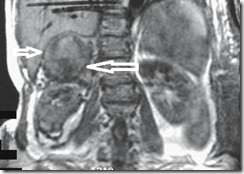

image

Bleeding pheochromocytoma (arrows) identified

on T1-weighted coronal image. Hypointensity surrounding

the right kidney represents a perinephric and paranephric

hematoma.